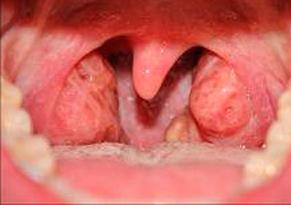

- воспаление миндалин;

- отечность слизистой горла, появление белесого налета или гнойничковых новообразований;

Одним словом, все симптомы характерны для гнойной ангины. С той лишь разницей, что стафилококковая инфекция плохо поддается лечению антибиотиками и может мигрировать в другие органы, в том числе и суставы.